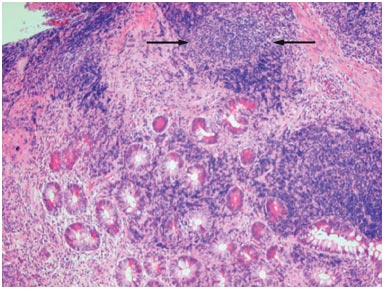

En effet, l’anomalie histologique spécifique de la maladie de Crohn est le granulome épithélioïde et giganto-cellulaire (Figure n°1) qui est le plus souvent présent dans une muqueuse saine en apparence. Il est très rarement mis en évidence lors de la première poussée. Il est mis en évidence seulement dans 30 % à 50 % des cas au cours de l’évolution de la maladie. Les fissures « transmurales » histologiques sont aussi assez caractéristiques de la maladie de Crohn.

Figure n° 1 : Granulome (Flèches) dans la maladie de Crohn

(Source Nature Clinical Practice Gastroenterology & Hepatology (2007) 4, 347-351)